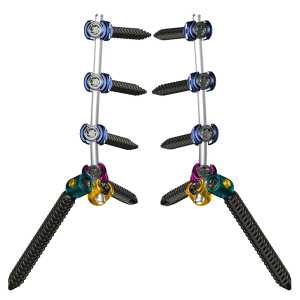

The Tiger Spine fixation system offers a comprehensive variety of implant and instrument options to build constructs from ilium to occiput.

- Polyaxial, monoaxial, uniplanar, fracture, & reduction screws

- Straight and pre-lordosed, titanium and cobalt chrome rods with hex or rounded ends and etched lines for rotational reference

- Screw diameters: 4.5mm – 10.5mm

- Screw lengths: 25mm – 120mm

- Rods: 35mm – 500mm

- Lateral connectors: neutral, 75°, & 105°